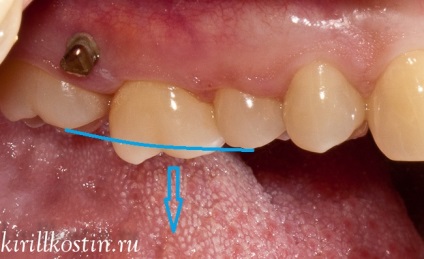

Egy nagyon gyakori helyzet választottuk példaként. Beteg rég elveszett hatodik alsó foga. Végül úgy döntöttem, néhány évvel visszaállítani segítségével az implantátumot. Ő került a klinikán városunkban, de ez a hely rá a korona nem volt elég. Ez azért történt, mert a „delete” az üres térben a felső „hat”. És ez egyértelműen látszik a fotón.

A javaslat a fájl a fogat orvos beteg otkzalas, és van a kollégáimmal. Ennek eredménye, hogy közösen úgy döntött, hogy ezt a fogat nagyon is lehetséges, hogy hajtsák végre a hátsó segítségével mini-implatov. Hogyan történik ez?

Nos, utána jön a fogszabályzó. Dr. Kostin ragasztott a fogak speciális gomb-kampók és gumiszalag kötötte ezeket horgok a feje a mini-implantátumok. Így nézett ki a bukkális oldalon.

És ez a része az ég:

Azt az irányt jelöli a erő vektor, amely csatlakozik a rugalmas gumiszalagot fogat. Mini implantátumok végre ebben az esetben a támogatást. Most már csak azt kell időszakosan változó megereszkedett gumi orvosnál, és kövesse a mozgást a fog. Mértékétől függően elmozdulásának a fog a kezelés tarthat 2-3 hónap 7-8.